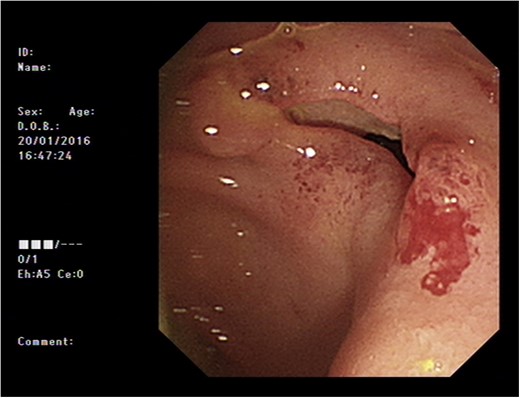

Initial upper GI endoscopy failed to enter the duodenum due to residue within the stomach with the appearance and odour of faeces noted. Abdominal computed tomography (CT) suggested a cavity with adherent ileum adjacent to the second part of the duodenum (Fig. 1). A contrast study was then undertaken demonstrating rapid flow of contrast into the terminal ileum and caecum originating from the duodenum (Fig. 2). Repeat upper GI endoscopy demonstrated an abnormal fungating fistulous communication between the duodenum and terminal ileum which permitted the full insertion of the endoscope (Figs 3 and 4). Biopsies were consistent with diffuse B-cell lymphoma (DLBCL) in accordance with the WHO classification.

Oral contrast study showing transit of barium into the ileum from a duodenal source through a cavity (arrow indicates cavity arising from duodenum).